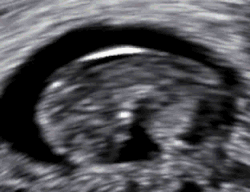

- Soms weet een vrouw nog niet dat de vrucht in haar buik is overleden. Vaak komt zij erachter bij de eerste echo, die vanaf 2007 tussen de 8e en 11e week van de zwangerschap wordt gemaakt door de verloskundige of de gynaecoloog. Het hartje van de foetus klopt dan niet, en soms is de foetus niet eens waar te nemen en ziet men enkel een lege vruchtzak. Vaak is in dit soort gevallen de foetus al een aantal weken dood. Men spreekt dan van een missed abortion. Er zijn dan verschillende mogelijkheden: afwachten tot de miskraam op natuurlijke wijze op gang komt; met behulp van medicijnen de uitstoting van het overleden vruchtje opwekken; een zuigcurettage laten doen door de gynaecoloog in het ziekenhuis.